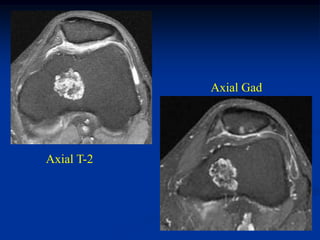

Case #588

22 year male

periosteal chondroma

femur